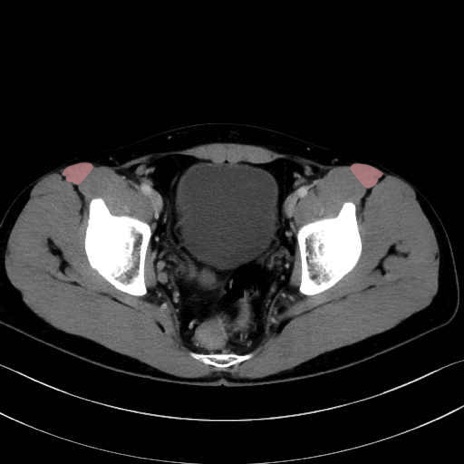

大腿筋膜張筋 (Tensor fasciae latae)

縫工筋 (Sartorius)